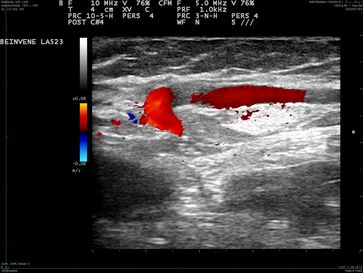

Platzierung des Radiofrequenzkatheters 1 cm vor Einmündung der Vena saphena magna in die Vena femoralis. Der Durchmesser der Vsm beträgt 7 mm.

Nach Energieapplikation ist der Durchmesser der Vsm auf 2 mm geschrumpft, das Lumen verschlossen.